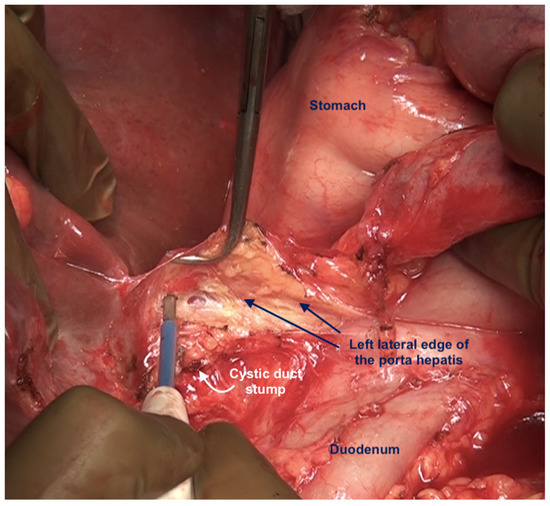

6.5. Lesser Omentectomy and Hepatoduodenal Ligament Clearance

6.6. Foramen of Winslow and the Posterior Layer of the Hepatoduodenal Ligament

| Hepatoduodenal ligament | This is the peritoneum overlying the porta hepatis extending from the lateral border of the common bile duct to the medial border of the portal vein and the lower end of the umbilical ligament to the superior border of the first part of the duodenum. The common bile duct, the hepatic artery, and the portal vein are encased in this peritoneal fold. | |